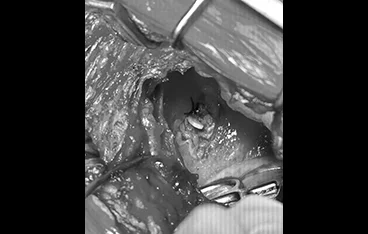

📍 폐엽절제

폐엽절제 전

폐엽절제 후

정확한 진단과 수술로 삶의 질을 회복합니다